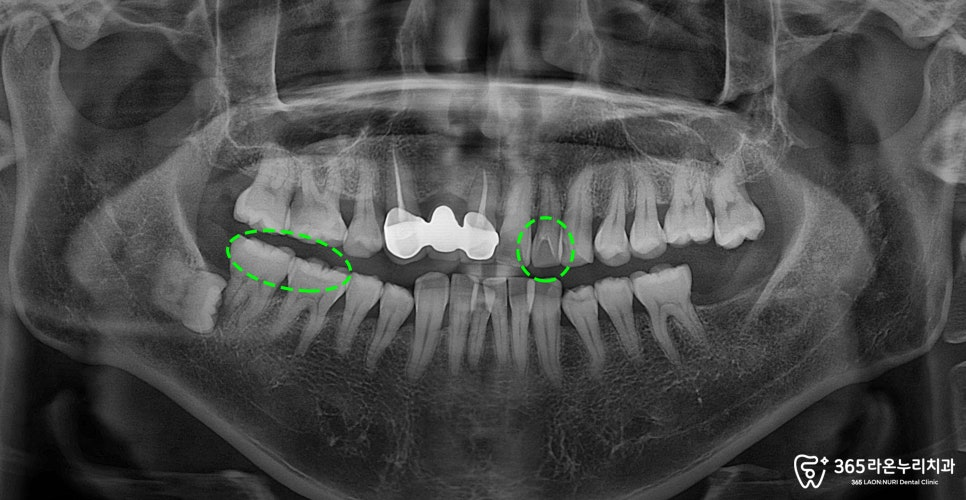

치과 정기 검진에서는 단순히 눈으로만

보는 것이 아니라, 엑스레이 촬영을

통해 눈으로 보기 어려운 문제까지

확인할 수 있습니다.

예를 들어

-치아 뿌리 속 염증 유무

-사랑니의 위치와 문제가 있는지

-보철 상태

등을 확인할 수 있습니다.

특히 사랑니는 겉으로 아무 문제가 없어보이지만

잇몸 속에 매복되어 문제가 생길 수 있기에

검사하는 것이 중요합니다.

지금으로써는 오른쪽 아래턱에

누운 사랑니가 관찰되고 있었습니다.

이렇게 사랑니가 누워서

자라고 있는 경우 인접한

어금니를 지속적으로 밀게 되면서

염증을 유발하는 원인이 될 수 있습니다.